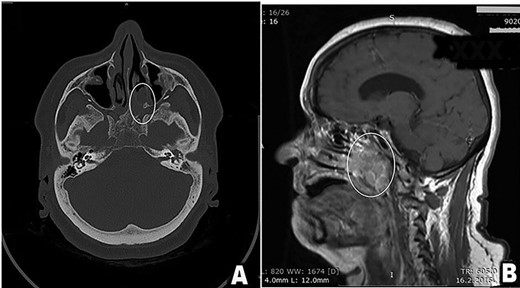

A 61-year-old female patient presented with history of disease lasted for 5 years before hospital admission. Symptoms included nasal obstruction with consecutive conductive hearing loss, hyposmia, nasal discharge and nasality in speech. Nasal endoscopic examination showed a tumor mass in the posterior part of the left nasal cavity occupying both sides of the nasopharyngeal space. Multi-slice CT scan and MRI revealed a destructive tumor mass 4 × 5 cm primary located in the region of paranasal sinuses on the left side with suspected tumor spread in the nasopharynx, upper parapharyngeal space and petroclival region with rather extensive skull base involvement, as it is demonstrated in Fig. 1.

(A and B) Preoperative scan (A-axial CT scan, B-sagittal MRI scan). Multi-sliced CT and MRI scan revealed a destructive mass 4 × 5 cm in the posterior third of the left nasal cavity, left ethmoid and left maxillary sinus spreading into nasopharynx predominantly on patients left side, but occluding both choanae (tumor in white oval). Tumor spread included left great wing of the sphenoid bone, along the left petroclival fissure and the apex of the left temporal bone.